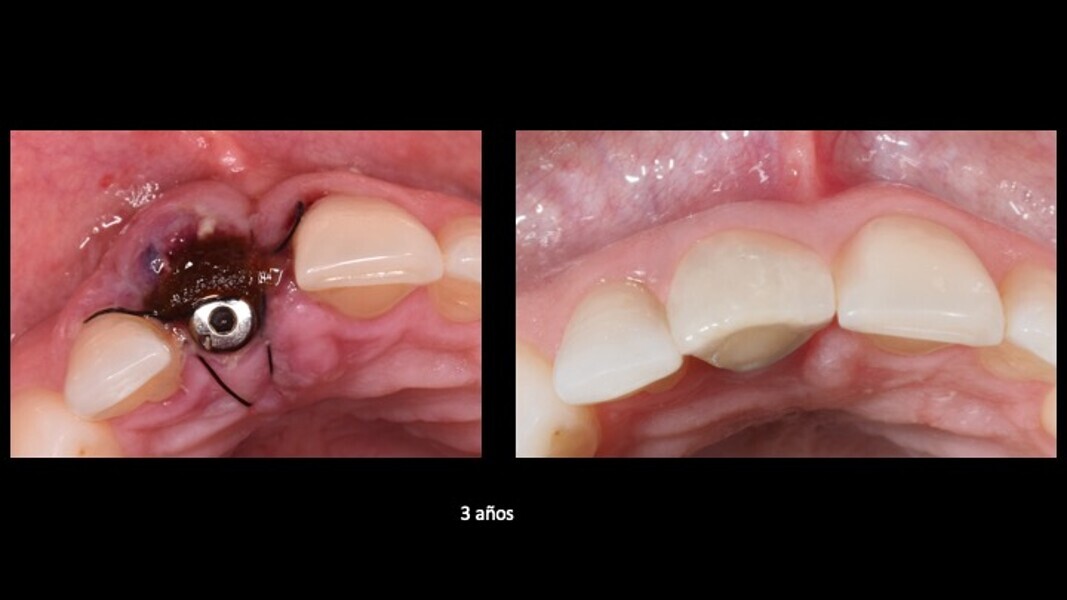

Figuras 21 y 22. Imágenes del día de la intervención y a los 2 años de evolución. Se observa una regeneración casi completa del periodonto, a pesar de presentar un defecto óseo inicial muy importante en la tabla ósea cortical vestibular. Con esta técnica solucionamos en un solo acto quirúrgico, tanto la preservación como la regeneración ósea, con gran estabilidad de los resultados en el tiempo.

Figuras 21 y 22. Imágenes del día de la intervención y a los 3 años de evolución. Se observa una regeneración casi completa del periodonto, a pesar de presentar un defecto óseo inicial muy importante en la tabla ósea cortical vestibular. Con esta técnica solucionamos en un solo acto quirúrgico, tanto la preservación como la regeneración ósea, con gran estabilidad de los resultados en el tiempo.